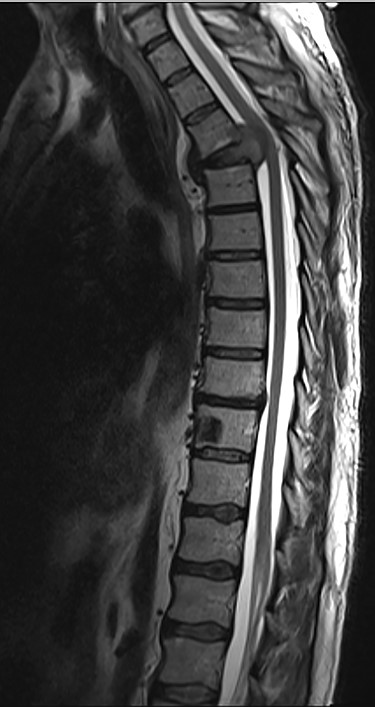

Sagittal T2-weighted magnetic resonance image (T2W MRI) with T4 metastatic epidural spinal cord compression (MESCC) and a synchronous T10 lytic lesion.